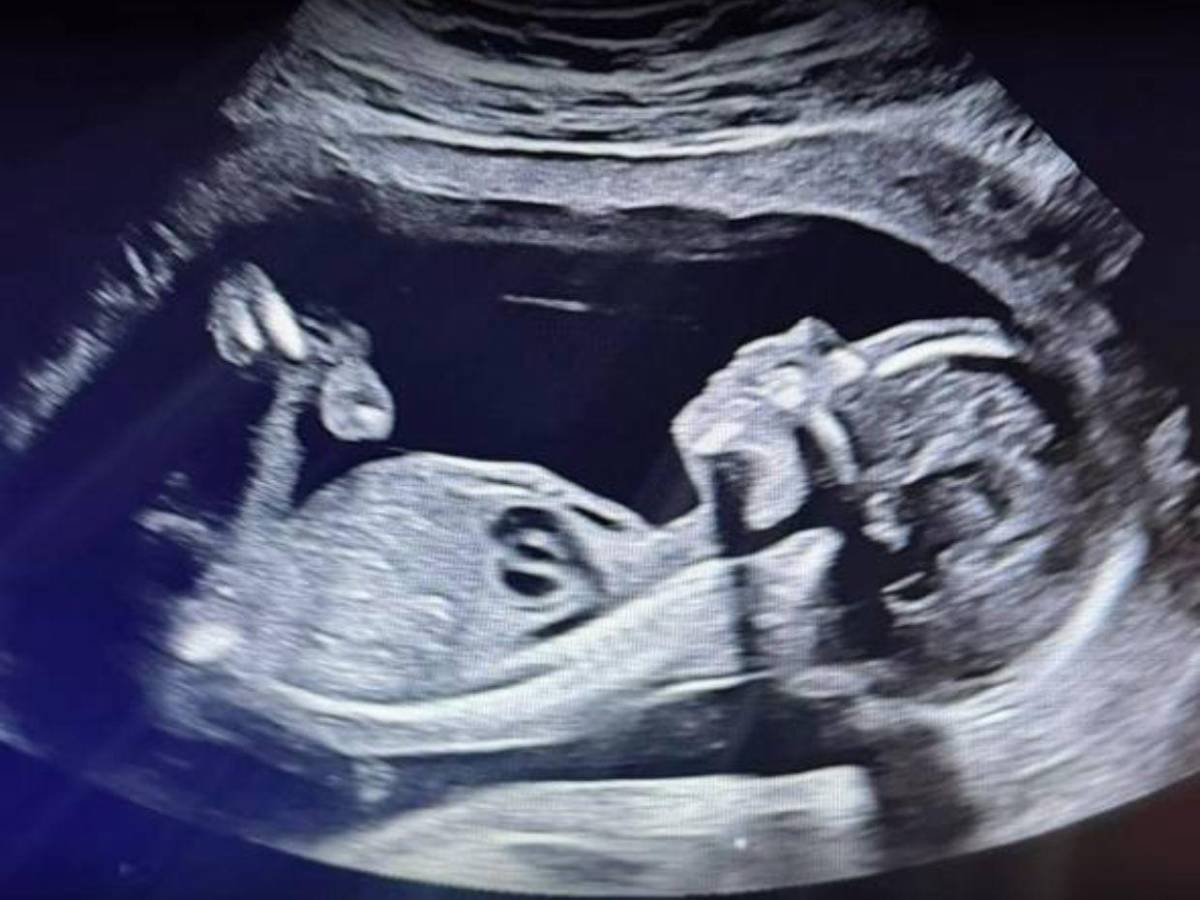

También incluyeron videos de los primeros ultrasonidos y la reacción de familiares y amigos cercanos, quienes se mostraron visiblemente emocionados.